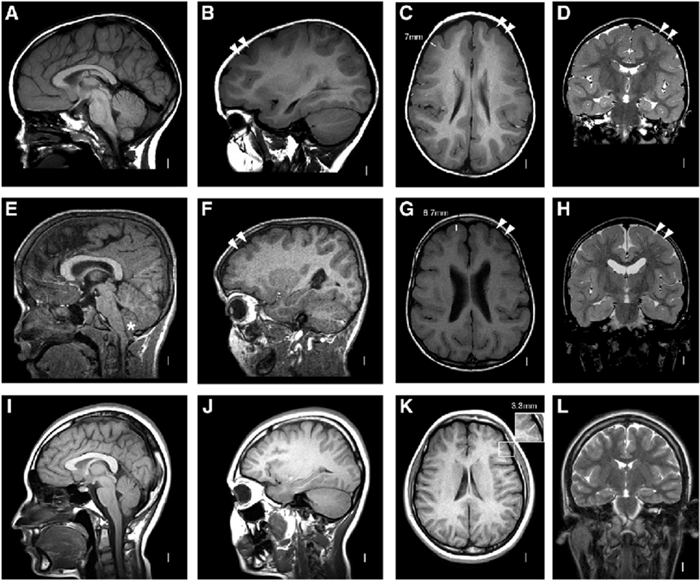

Как распознают рассеянный синдром на снимках? При рассеянном склерозе на снимках заметно характерно типичное распределение очагов в белом веществе головного мозга. Кроме того, для данного диагноза характерно поражение мозолистого тела, дугообразных волокон, височных долей, мозгового ствола, мозжечка и спинного мозга. Такое распределение очагов нехарактерно для иных патологических процессов, поэтому трудностей при постановке диагноза обычно не возникает. При ангиопатии возможны поражения ствола мозга, однако они обычно симметричны и располагаются центрально, в то время как очаги при рассеянном склерозе локализованы по периферии.

Признаки рассеянного склероза на МРТ головного мозга манифестируют себя следующим образом:

- появлением новых очагов и увеличением старых;

- во время обострения проведение МРТ головы с контрастом будет приводить к тому, что очаги демиелинизации будут накапливать контраст причудливым кольцевым способом.

На изображениях, получаемых посредством МРТ при рассеянном склерозе, диагност четко видит:

- более интенсивный сигнал, что на картинке выражено наличием очага или очагов

- общее количество очагов

- расположение очагов и их близость к важным структурам головного мозга.

Основные признаки РС:

- Обнаружение очагов демиелинизации в церебральных структурах является безусловным подтверждением диагноза PC.

- При спинальной форме PC на МРТ головного мозга выявляются множественные церебральные очаги, даже при минимальных клинических симптомах поражения головного мозга.

- Наиболее характерными MP-критериями стволовой формы PC является визуализация активных очагов в стволовых структурах, выраженные атрофические изменения и расширение ликворных цистерн.

- При ремиттирующих формах РС на ранних этапах отмечается наличие большего количества очагов крупных размеров, локализующихся в функционально значимых анатомических структурах, включающих ствол, мозжечок. На ранних сроках заболевания при этом типе течения наблюдается расширение желудочков и субарахноидальных цистерн.